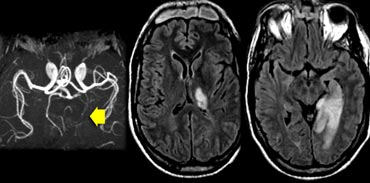

The images show bilateral thalamic infarctions - lesions often associated with cognitive dysfunction.

Transverse FLAIR images in two different patients. Transverse FLAIR images in two different patients.

Study the images of two different patients.

The image on the far left shows an infarct in the vascular territory of the Posterior Cerebral Artery (PCA), with involvement of the inferior medial temporal lobe which includes the hippocampus.

This is a strategic infarction, since it is in the dominant hemisphere, it will result in cognitive dysfunction.

The image next to it is a transverse FLAIR image showing another infarct in the PCA-territory, with involvement of the temporo-occipital association area.

This is another example of a strategic infarction that can result in cognitive dysfunction.